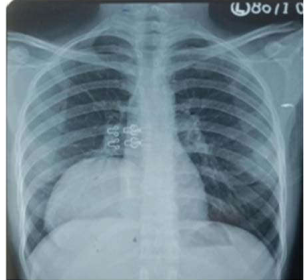

Chest X-ray showing lung hydatid cyst

Description: No description available.